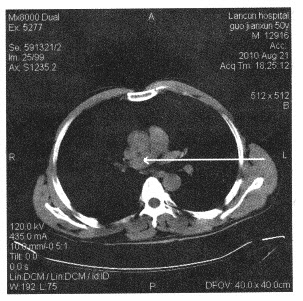

下面胸部断层图像中箭头所指为()

A:主动脉弓

B:肺动脉干

C:右肺动脉

D:上腔静脉

E:纵隔淋巴结